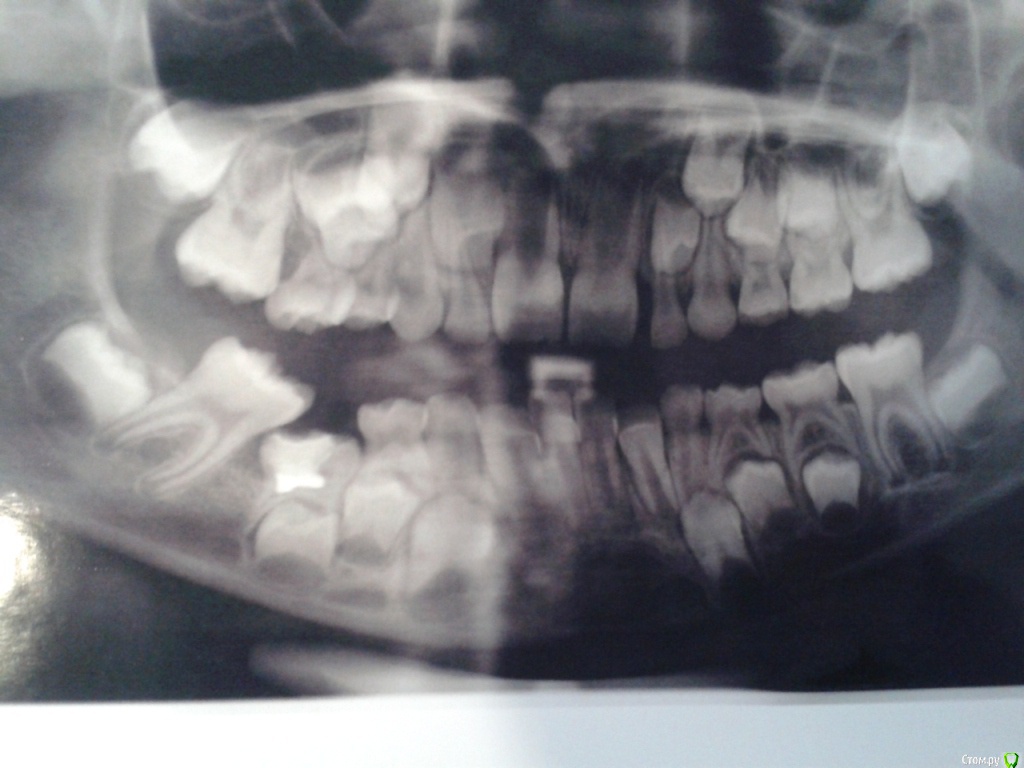

С лета 2014 г. начал прорезываться нижний правый зуб 5-ка. До настоящего времени зуб находится по своей высоте в десне. Так как этот зуб по площади своей поверхности находился на 30-40% под десной, то начал появляться кариес. Ребенку было три года и вычищать досконально было очень тяжело. Заметив темное пятно, обратились к терапевту. Нам без снимка сказали, что это пульпит и тому подобное. Кроме того, с тех пор ребенок отказался посещать врача – испугалась. Грубое обращение. Впоследствии образовалась полость. Кариес. Обратились к другому терапевту, который поставил диагноз «пульпит». Сделали снимок, который показал анкилоз. Ортодонт и терапевт сомневались в лечении зуба, предлагая его удалить. Ортодонт высказывала опасения, что удаление тоже опасно, так как прямо под корнями этого зуба расположен постоянный зуб. Говорила, что зуб уже никогда не прорежется. Терапевт предлагала попробовать спасти зуб. Убрать нависающую часть десны и пролечить пульпит, поставить пломбу.

По снимку сказали нет зачатков каких-то постоянных зубов. Это наследственное по моей линии. Глубокий прикус, в дальнейшем требуется ортодонтическое лечение

Через год начал прорезываться зуб, стоящий рядом с пролеченным. Прорезался и… наклонился. Теперь он ушел в наклон с одной стороны, закрывая при этом часть поверхности 5-ки. Наплыла десна, но не критично. С одной стороны зуб полностью вырос, с другой – в десне.

Прилагаю снимки. Один до того, как прорезался наклоненный зуб. Второй - после его прорезывания и лечения зуба с анкилозом. Прошу прощения за качества некоторых снимков.

Пломба на снимках имеет розовый, почти красный цвет.